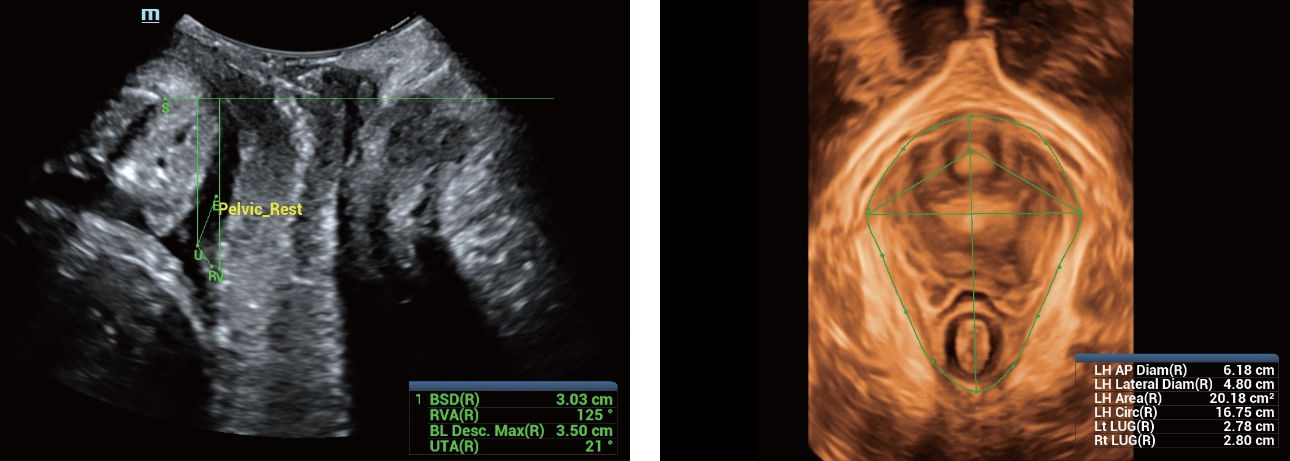

?? ??? ??

?? Resona 7? ???? ??? ?? ???? ??? ??? ???? ??? ?? ???? V Flow? ?? CNS ??? ?? 3D ??? ???? ?? ???? ?? ??? ?? ?? ?? ??? ??????. ???? ??? ??? ?? ?? ??? ??? ?? ?? ??? ??? Resona 7? ??? ???? ???? ??? ??? ??? ????.